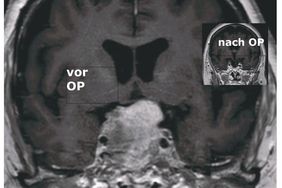

Ist die Erkrankung durch eine MRT-Untersuchung eindeutig diagnostiziert, wird das Adenom in der Regel durch die Nase endoskopisch entfernt. „Die Patienten bleiben nach der OP lebenslang unter Kontrolle, aber nur in ganz seltenen Fällen kommt der Tumor wieder“, erklärt PD Dr. med. habil. Michael Fritsch, Chefarzt der Klinik für Neurochirurgie. Über die interdisziplinäre Diagnostik und Therapie des Hypophysenadenoms spricht er beim Gesundheitsforum DBK am 23. März 2026 um 17 Uhr im Konferenzraum des Hauses G (Bethesda Klinik) in Neubrandenburg.